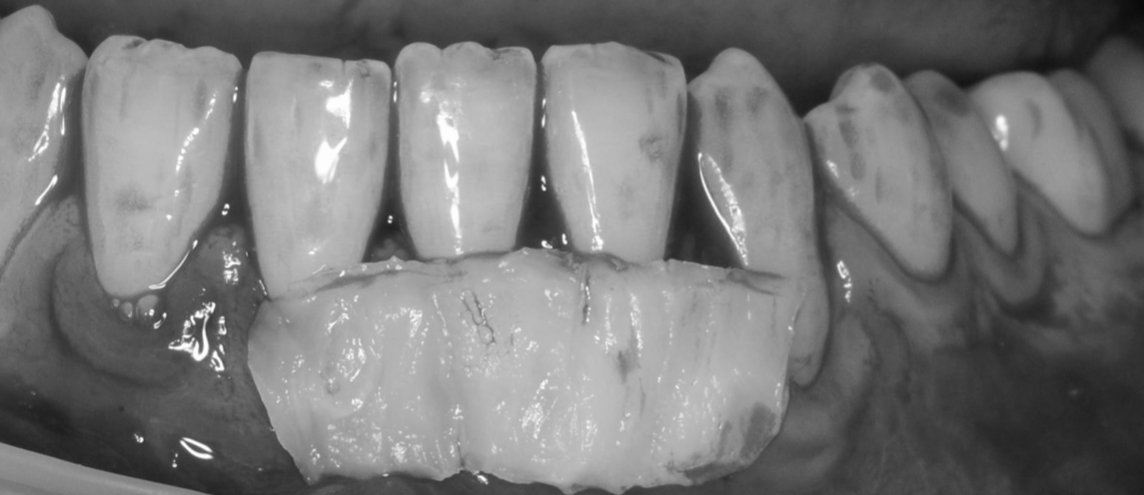

Os enseñamos este nuevo caso el Dr. Arturo Sánchez Colodro en nuestra clínica dental de Jaén, nos muestra un caso donde se puede apreciar con mucha claridad el antes y después de un caso de recesiones inferiores. Este caso ha sido tratado con la última y más avanzada tecnología en digitalización dental.

Exploración intraoral inicial:

Fotografías del proceso: